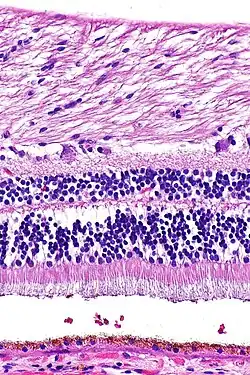

H&E is the combination of two histological stains: hematoxylin and eosin. The hematoxylin stains cell nuclei a purplish blue, and eosin stains the extracellular matrix and cytoplasm pink, with other structures taking on different shades, hues, and combinations of these colors.[5][6] Hence a pathologist can easily differentiate between the nuclear and cytoplasmic parts of a cell, and additionally, the overall patterns of coloration from the stain show the general layout and distribution of cells and provides a general overview of a tissue sample's structure.[7] Thus, pattern recognition, both by expert humans themselves and by software that aids those experts (in digital pathology), provides histologic information.

Hematoxylin principally colors the nuclei of cells blue or dark-purple,[6][15][14] along with a few other tissues, such as keratohyalin granules and calcified material. Eosin stains the cytoplasm and some other structures including extracellular matrix such as collagen[5][7][14] in up to five shades of pink.[8] The eosinophilic (substances that are stained by eosin)[5] structures are generally composed of intracellular or extracellular proteins. The Lewy bodies and Mallory bodies are examples of eosinophilic structures. Most of the cytoplasm is eosinophilic and is rendered pink.[10][15] Red blood cells are stained intensely red.

Lung tissue taken from an emphysema patient. Cell nuclei (blue-purple), red blood cells (bright red), other cell bodies and extracellular material (pink), and air spaces (white).- Muscle tissue, cell nuclei (blue-purple), cell body (pink)